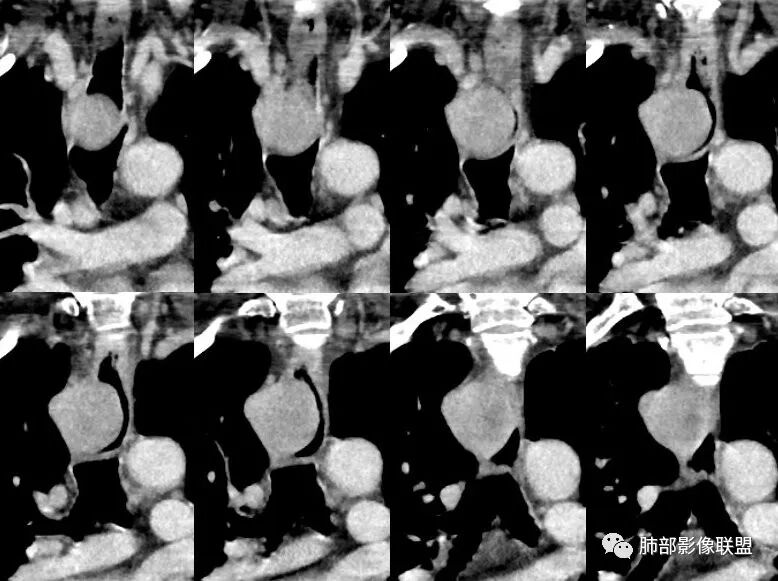

术中示:肿块位于右前上纵膈,奇静脉弓上3cm,大小约30mm×30mm,来源于食管;经腋前线第3肋间12cm操作切口,切开纵膈胸膜,纵形切开食管肌层,肿瘤基底部与食管黏膜粘连致密,将肿块大部分切除,送术中快速病检示:梭形细胞瘤可能。因肿瘤基底部较宽,且与食管黏膜粘连致密,无法与黏膜完全分离,黏胲残留少许肿瘤组织,将电刀烧灼肿瘤基底部表面,将肌层间断缝合

2.定位:右后上纵隔肿块,与食管关系密切,边缘光滑,冠状位显示肿块与食管壁结构相顺延,上下径大于横径,呈现跨管壁内外生长倾向,食管管腔狭窄,而气管腔内未见突入,因此食管来源肿块可能大。

4.肿块渐进性强化,局部可见低强化区(下图红箭头所示),可以符合神经鞘瘤AB区的影像特点,尽管该部位神经鞘瘤罕见,毕竟食管壁也是有神经走行的,解剖也提示诊断的方向。